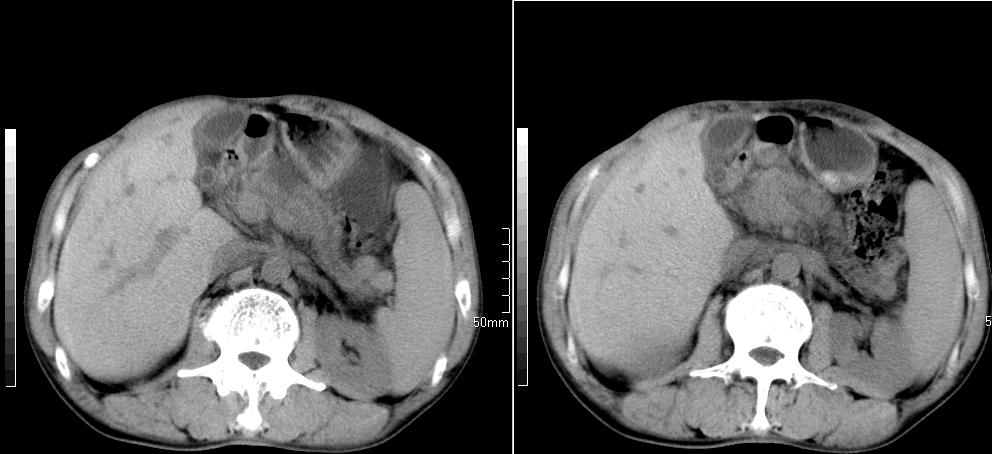

标题: CT26769:男,58岁,腹胀、腹部不适一年余 [打印本页]

标题: CT26769:男,58岁,腹胀、腹部不适一年余

肠系膜脂膜炎,胆囊炎,脾大。建议结合临床。鉴别:慢性胰腺炎并假囊肿形成。

1 慢性胰腺炎并假囊肿形成。2 慢性胆囊炎并累及肝边缘!

1)考虑慢性胰腺炎并假性囊肿形成。2) 慢性胆囊炎。3)肝内胆管扩张。

支持1 慢性胰腺炎并假囊肿形成。2 慢性胆囊炎。

1肝内胆管扩张,性质待定,2慢性胰腺炎胰管扩张,胰腺颈部假囊肿,3肝左叶低密度为小囊肿,4胆囊炎。

1)考虑慢性胰腺炎并假性囊肿形成。2)肝内胆管稍扩张。